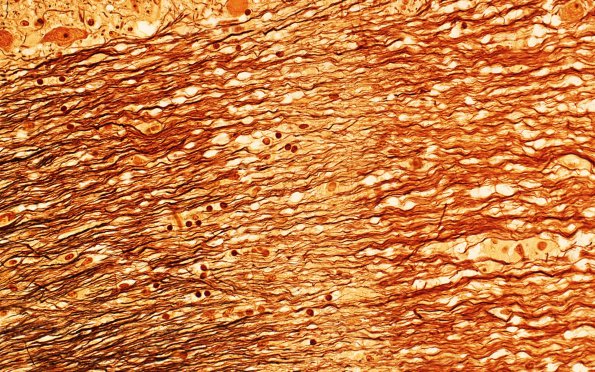

Washington University Experience | MYELIN (IMMUNE-MEDIATED) | MS - Brainstem & Cerebellum | 3B8 MS (Case 3) N11 Biels 40X 1

This 40X image show transversely oriented axons (area of arrow from 3B6). Although axons are clearly still present in this demyelinated tract, significant axon loss has occurred (Bielschowsky)